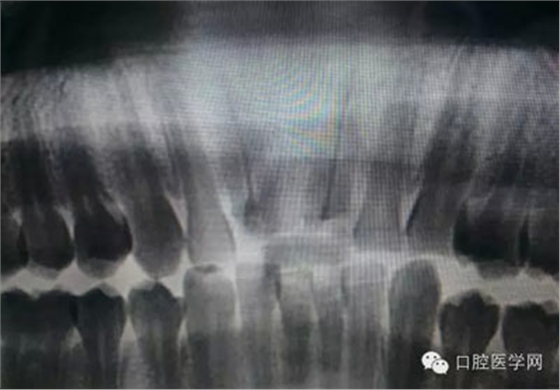

根管治療,我們?cè)诖髮W(xué)的時(shí)候就學(xué)習(xí)的東西,標(biāo)準(zhǔn)就在那里放著,可是很多時(shí)候我們熟視無(wú)睹,放任我們的想象去做。我們多些重視,多些心思,會(huì)好很多,認(rèn)真對(duì)待每顆牙齒。